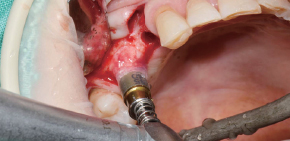

使用Ø3.5/4.0 Harvesting Drill的临床案例。

by Dr. Soohong Kim, DDS, Ph.D

确认种植体和采集部位后,一边注水一边以300rpm的速度钻孔。

根据不同的骨高度贴紧Silicone Shield,防止骨片遗失。

通过透明的Silicone Shield轻松地确认骨采集量。

在钻头上分离Silicone Shield和塞子后,将采集好的骨片放到Bone Dish中。

植入种植体后连接愈合基台,在缺损部位进行GBR。

*采集的第二部:钻孔4mm后,若塞子和Silicone Shield中装满了骨片,则将采集好的骨片放到Bone Dish后更换为7mm钻。